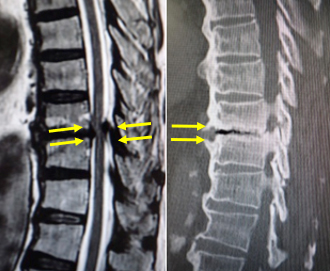

びまん性特発性骨増殖症や、強直性脊椎炎という、せぼねが連続して癒合(くっつく)してしまう病気があります。脊椎が癒合していない部分で狭窄を生じたり、軽微な外傷でも骨折を起こし、脊髄を圧迫して神経障害が出現することがあります。当院では、体にかかる負担の少ない経皮的椎弓根スクリューを用いた特殊な方法で、脊椎を安定化させるミスト手術を積極的に行っております。

があり、同部位で狭窄が生じ脊髄が圧迫されています。

に脊椎を安定化し、神経症状は著明に改善しました。